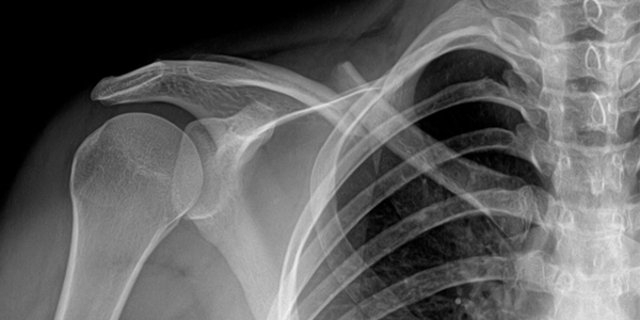

35 yaş – Kemikler: Kemik kütlesi 35 yaşından sonra %1’lik bir oranla düşüşe geçiyor (menopozdan sonra da hızlanıyor). Ağırlık kaldırma egzersizleri kemik yoğunluğunda büyük fark yaratıyor.

2015 tarihli bir çalışma günde 20 kez zıplamanın bile leğen kemiğinin mineral derişimini iyileştirdiğini ortaya koyuyor.